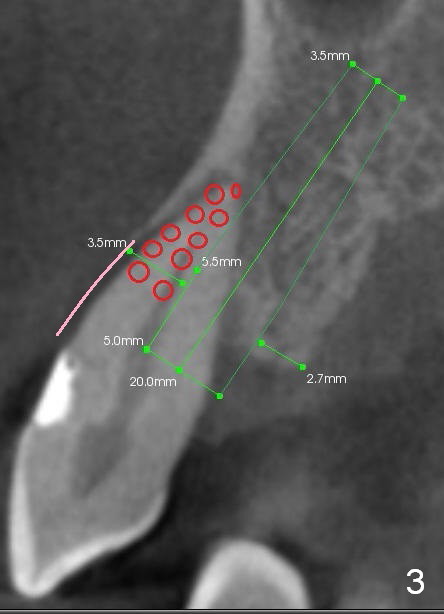

A 65-year-old man has history of Type II diabetes and stroke. He is taking a blood thinner (Xarelto 20 mg qd). The tooth #11 has been mobile for several years. Fig.1 is a CBCT taken 2 years 8 months earlier. The affected tooth has now supraerupted (Fig.2 arrow) with apical abscess (arrowhead).

Bone defect at present should be more severe than CBCT coronal (Fig.3) and axial (Fig.4) sections indicate. After palatal placement of a 5x20 mm tissue level implant (Fig.3 green area) and an appropriate abutment, an immediate provisional is to be fabricated. A block graft is harvested from #12 edentulous region (buccal plate) to the buccal defect at the site of #11 (Fig.4 curved light blue arrow). Prepare surgical handpiece and chisels. The remaining bony defect will be filled with allograft and Osteogen (red circles). The graft site is going to be covered by Osteotape (Fig.3,4 pink curved line), while the donor site is given mixture of allograft and Osteogen and Collagen Dressing. When the soft tissue deficiency is found, connective tissue graft is to be harvested from the palate. If visibility is compromised for these steps, an incision will be made as shown in Fig.5. This should be done with caution considering the medical conditions. Before surgery, ask the patient whether the blood thinner has stopped for a few days or not and how diabetes control is.